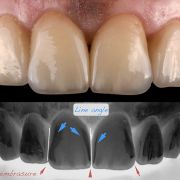

The patient was complaining of heavy stain and multiple faulty restorations. Considering the age in analyzing the teeth shape, contour and color play a vital role in success. Root canal treatment was done for the anterior teeth (Dr Khalid Merdad). Veneers and crowns @perlasmile lab.